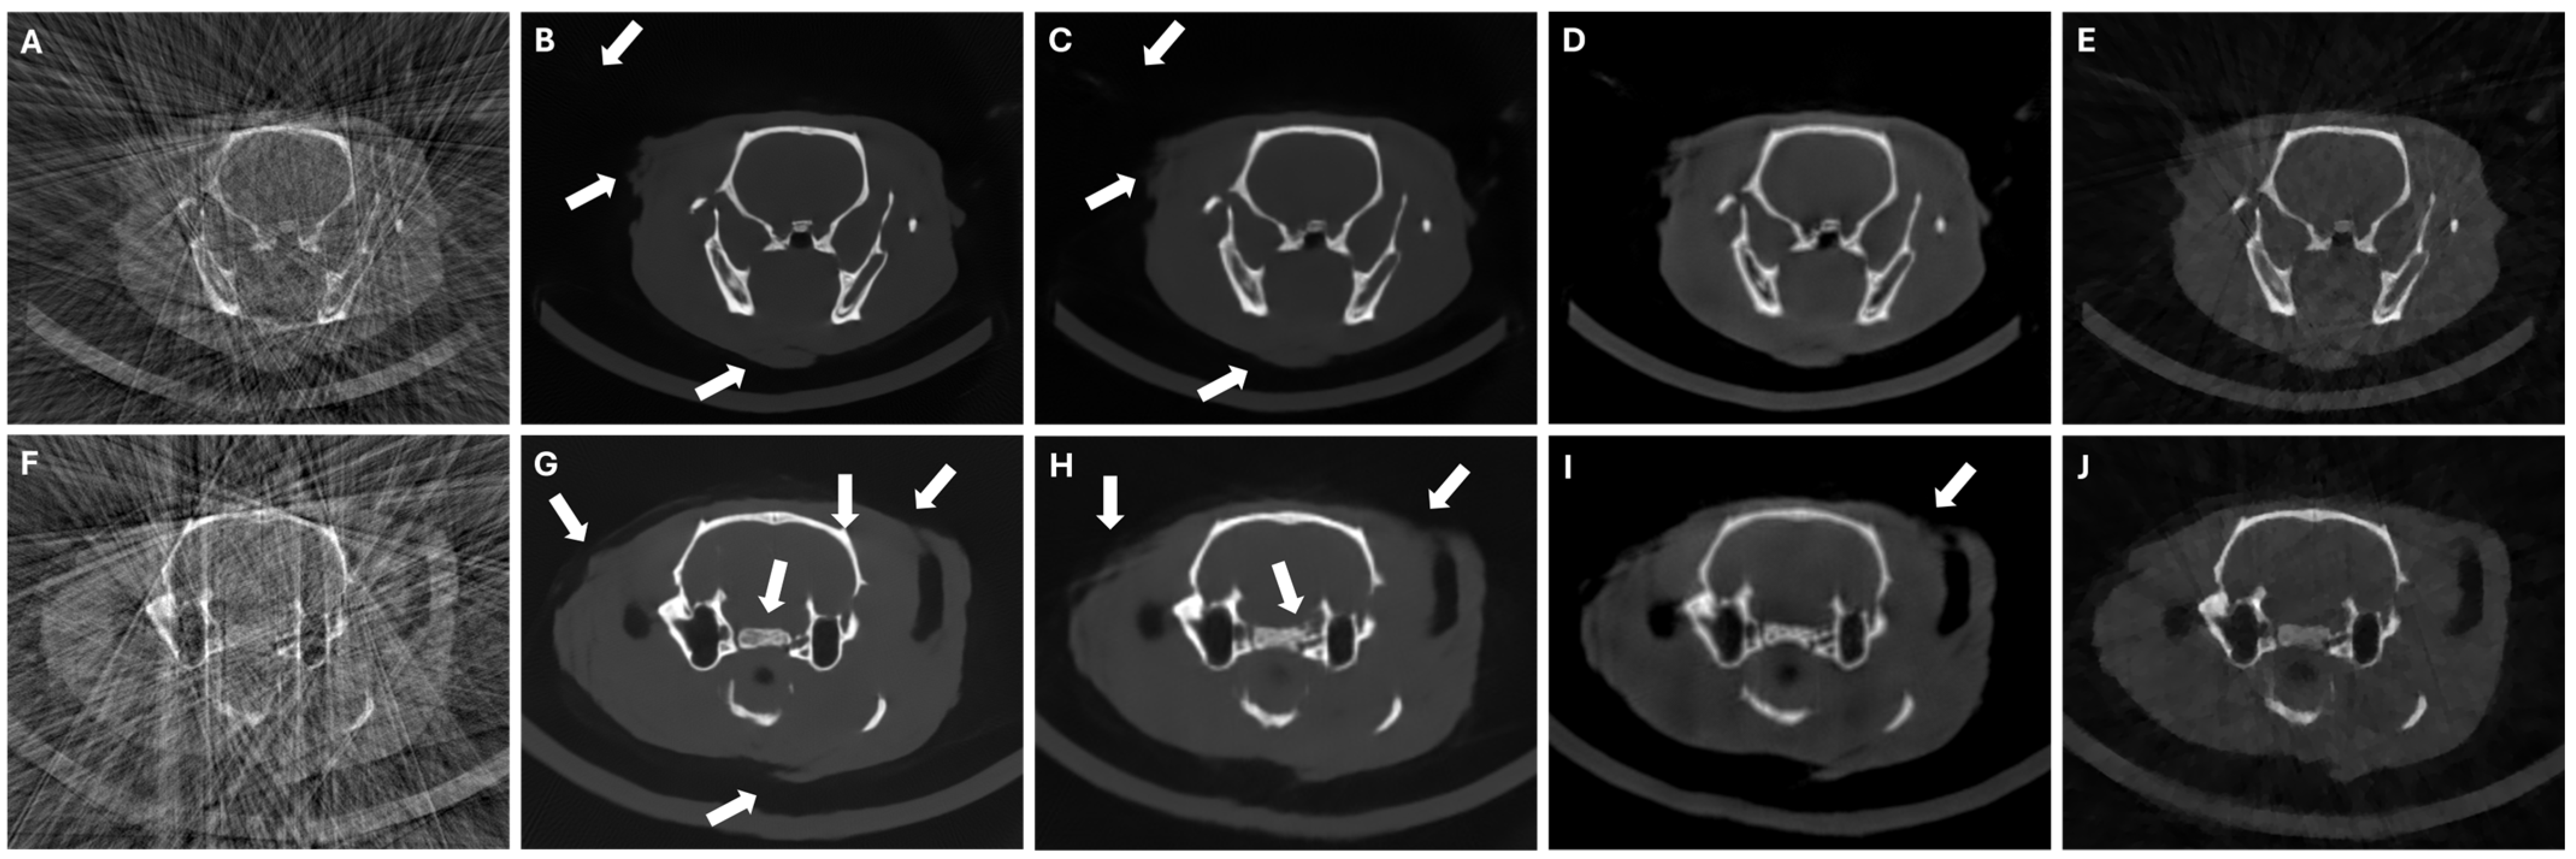

3.4. Results in Highly Limited-Data Scenarios